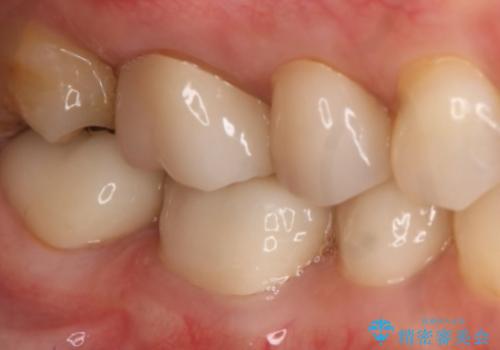

- 右上7番の銀歯のやりかえを主訴に来院された患者様です。

切削量・形態を考慮し、セラミックインレーでの治療を計画しました。

インレー治療では自分の歯を多く残すことが出来ます。